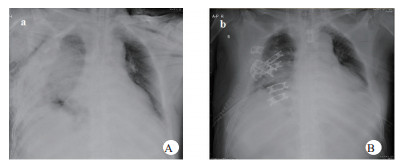

1 资料与方法患者,男,63岁,因“车祸致呼吸困难1 d”入院。既往体健。患者于2019年9月30日翻车致胸部挤压性创伤,伤后出现极度呼吸困难,送至当地医院,测血压80/50 mmHg(1 mmHg=0.133 kPa),胸部CT提示右侧血气胸,给予输血补液、去甲肾上腺素维持血压,经鼻气管插管呼吸机辅助通气,放置胸腔闭式引流管2根。因循环及氧合维持困难,10月1日转至徐州医科大学附属医院,收入EICU。入院查体:T 36.7℃,P 152次/min,R 14次/min(机械通气支持),BP 110/67 mmHg[去甲肾上腺素0.5 μg/kg·min)维持]。处于镇静状态,双侧瞳孔等大等圆,直径约2.0 mm,对光反射未引出;全身多处皮肤软组织擦挫伤,颈部及前胸、上肢广泛皮下气肿,右侧胸壁显著塌陷,反常呼吸,听诊双肺呼吸音低;心率快、心律齐、心音不遥远;腹部无异常体征;2根胸腔闭式引流管引流通畅。入院当天CT检查显示:双侧肋骨骨折伴右侧胸壁塌陷,两肺挫伤、创伤性湿肺,右肺撕裂伤,右侧液气胸,双侧胸壁广泛皮下气肿(图 1:A, B, C);未见颅内出血及腹部器官损伤。入室后0.5 h血气分析:pH 7.18,PCO2 57.5 mmHg,PO2 67.1 mmHg,Lac 4.4 mmol/L,氧合指数67.1 mmHg,APACHE Ⅱ评分27分。治疗上予镇痛镇静、保护性肺通气策略、保温、预防感染等治疗,效果不佳,连枷胸,皮下气肿范围不断扩大,氧合指数持续<100 mmHg。于10月2日气管切开后行V-V ECMO治疗(右股静脉—右颈静脉);因右侧血胸、胸引量24 h达1 000 mL,血红蛋白下降,凝血功能显著异常,存在创伤性凝血病,采取无肝素抗凝ECMO技术,提高血流速(4.6 L / min),气流速(5 L / min),FiO2 100%;给予成分输血,监测ACT及APTT。ECMO转机1h后去甲肾上腺素停用,复查血气分析PO2 105 mmHg。此后,患者氧合和血流动力学逐步改善,创伤性凝血病已纠正,于10月7日在无肝素V-V ECMO支持下行“胸骨骨折切开复位钢板内固定术+右侧3、4、5前肋肋骨骨折环抱器内固定+右侧5、6、7、8后肋肋骨骨折环抱器内固定术+两侧胸腔闭式引流术”。术中见第5肋骨前端骨折向下外移位,3、4肋骨多段骨折,胸壁前上方完全塌陷,肺脏直接外露,胸腔内布满血凝块,术中取出血凝块共约1 000 mL。术后氧分压上升至400 mmHg,术后复查床边胸片,肺部影像学较前改善(图 2 A, B),继续无肝素V-V ECMO治疗1 d后,于10月8日开始肝素抗凝,维持ACT在160 s~180 s,APTT在40 s~50 s,肝素化期间无出血并发症发生。10月11日行自主氧合试验通过,予以撤机。10月12日复查胸部CT两肺复张满意(图 3 A, B),开始间断停用呼吸机并床边康复训练。10月28日撤离呼吸机,气切处高流量吸氧。11月15日拔除气切管。11月18日康复出院,无明显并发症发生。

| 图 2 A入院第一天床边胸片;B术后当天床边胸片。 |